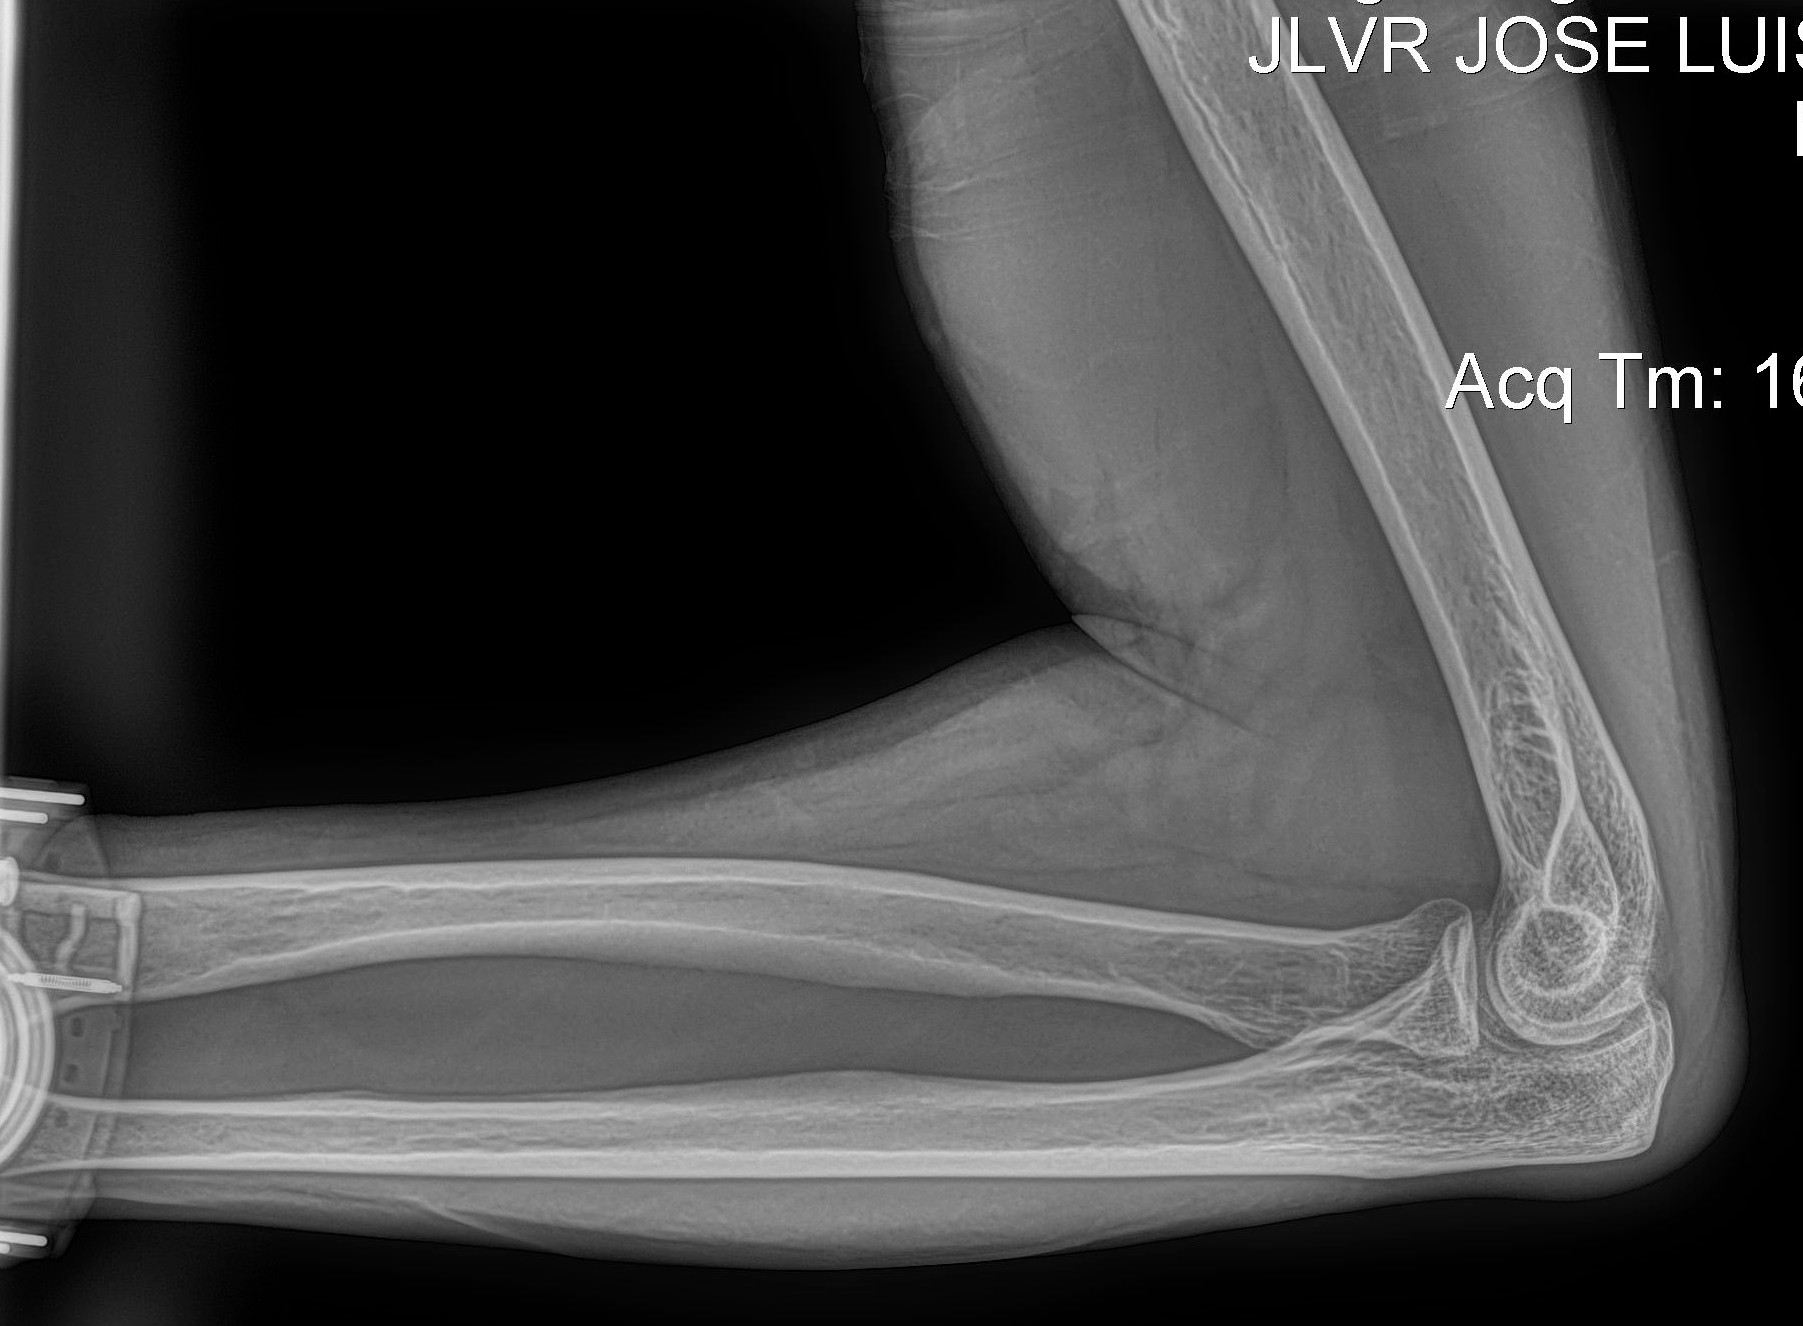

Cambios Térmicos en las Extremidades de Caballos,

Asociados a Golpes y su Evaluación por Termografía.

Los caballos de salto, en competencia, pueden derribar obstáculos y lastimarse. Si se golpean, no siempre claudican. Considerando al calor como un signo de inflamación, se evaluaron los cambios térmicos de 6 áreas de las extremidades torácicas y pelvianas de 23 caballos de salto en nivel de competencia de 1.05 a 1.60 m de altura, por medio de termografía durante 4 días de competencia (N=2208 áreas).